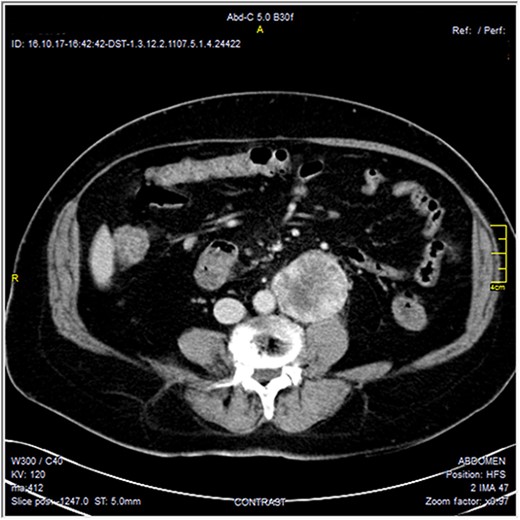

The CT scan was confirming the presence of a relatively well-defined retroperitoneal lobulated mass lesion seen extending along the left lateral wall of the distal abdominal aorta and left common iliac artery and anteromedial to the left psoas muscle. It showed heterogeneous intense peripheral enhancement during the porto-venous phase, the fat planes were preserved between the lesion and adjacent structures with no gross evidence of local invasion (Figs 1–3). The first diagnostic possibility was made as a retroperitoneal paraganglioma based on the CT appearance. The surgical decision of tumor removal was done.

Contrast-enhanced axial CT images—soft tissue window, show well-defined peripherally enhancing mass lesion at left para-aortic region. No local invasion.